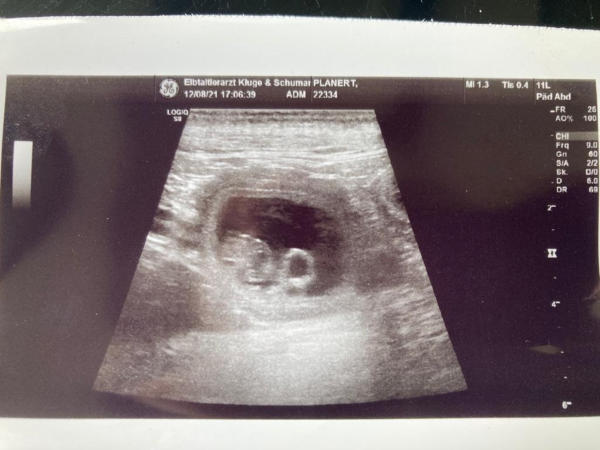

Maxim-Mathy de Domain de Val Kurlande, HD B2, ED 0, OCD frei deckte am 23.10.2021 Hera vom Promnitztal. Die Verpaarung ist DM und MD frei. Werte der Verpaarung: AVK 95,16 und IK 0,20. Ganz herzlich möchten wir uns bei Annette und Manni für die fantastische Betreuung bedanken.

Maxim-Mathy de Domain de Val Kurlande und unsere Hera werden Eltern. Wir sind in guter Hoffnung auf Christkinder.

2 Tage vor Weihnachten hat uns unsere Hera 6 kleine Christkinder beschert: Lasse und Lars, Lea, Lissi, Lara und Laura. Wir sind überglücklich. Der Vater: Maxim-Mathy de Domain de Val Kurlande HD B2, ED 0, OCD frei Werte der Verpaarung: AVK 95,16 und IK 0,20